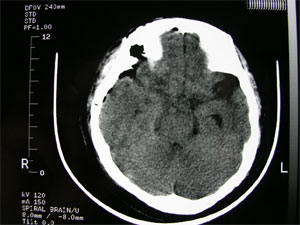

5.CT和MRI掃描 可確定腫瘤的部位和大小,絕大多數可作出定性診斷。CT掃描示邊界清晰的均勻高密度影,增強後顯著。少數呈混合密度或低密度改變。MRI見腫瘤多數呈等信號,增強後明顯強化。

蝶骨嵴腦膜瘤1.CT掃描 可見到以蝶骨嵴為中心的球形生長的腫瘤邊界清楚,經對比增強後腫瘤影明顯增強,如腫瘤壓迫側裂靜脈,腦水腫較顯著。